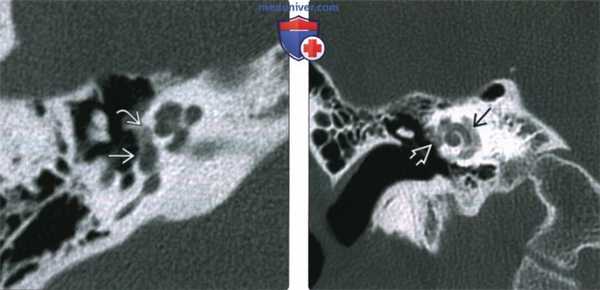

(Слева) При аксиальной КТ правой височной кости у молодого взрослого с прогрессирующей кондуктивной тугоухостью визуализируется типичная отоспонгиозная бляшка (фенестральный отосклероз) спереди от овального окна в области предполагаемой локализации щели перед окном.

(Справа) При корональной КТ правой височной кости у пациента со смешанной тугоухостью визуализируется рентгенонегативное «гало» вокруг улитки, обусловленное кохлеарным отосклерозом. Обратите также внимание на сопутствующий фенестральный отосклероз.

(Слева) При аксиальной КТ правой височной кости определяется бляшка смешанной структуры (со склеротическим и «прозрачным» компонентами) спереди от овального окна с вовлечением щели перед окном. Склеротическая часть бляшки при фенестральном отосклерозе обусловлена процессом заживления, рентгенопрозрачная часть - активным процессом.

(Справа) При аксиальной КТ левой височной кости визуализируется отоспонгиозная бляшка смешанной (склеротической и рентгено-негативной) структуры, приводящая к обструкции круглого окна. Отосклероз предрасполагает к невозможности протезирования стремечка и затрудняет кохлеарную имплантацию.